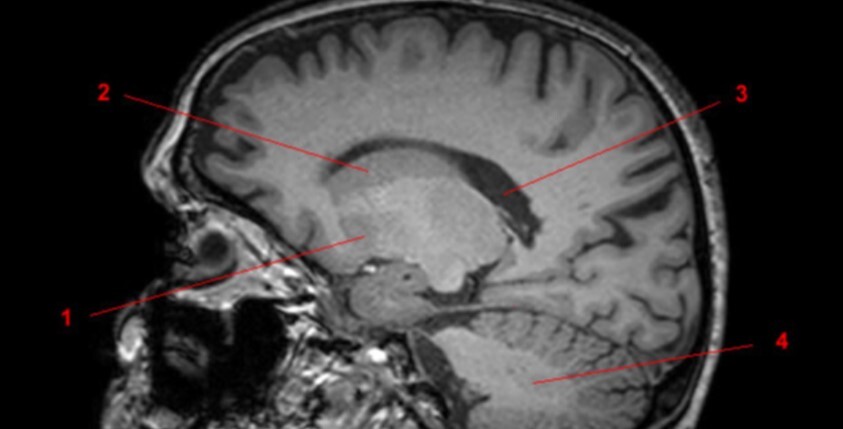

17

Q

Label 1-3

A

1-Lt Optic nerve

2-Optic chiasm

3-Rt Optic tract